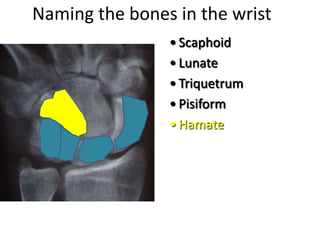

This document provides an overview of hand anatomy including:

- Naming the bones, joints, tendons, nerves and skin landmarks of the hand and wrist.